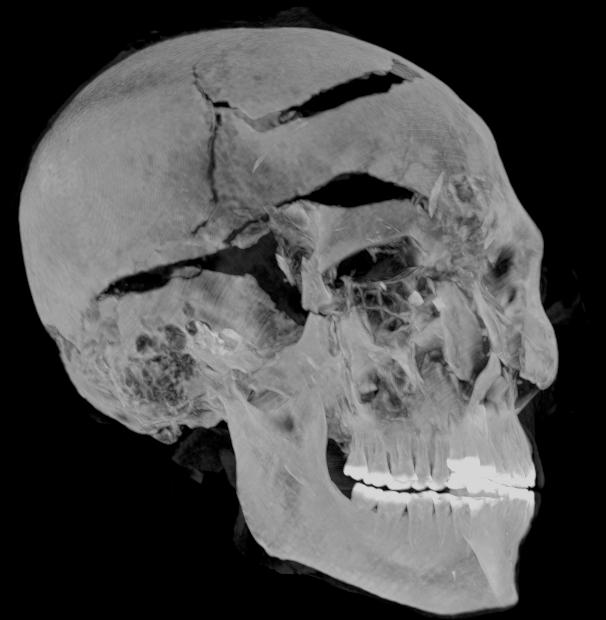

وفي بحثهما، قدم الباحثان المصريان زاهي حواس وسحر سليم تفسيرًا جديدًا للأحداث قبل وبعد وفاة الملك سقنن رع، استنادًا إلى صور الأشعة المقطعية ثنائية وثلاثية الأبعاد والتي تم تركيبها بواسطة تقنيات الكمبيوتر المتطورة، فيظهر تشوه الذراعين أنه يبدو أنه قد تم بالفعل أسر سقنن رع-تاعا  الثاني في ساحة المعركة، وقيدت يديه خلف ظهره، مما منعه من صد الهجوم الشرس عن وجهه.

وكشف التصوير المقطعي لمومياء سقنن رع تاعا الثاني عن تفاصيل دقيقة لإصابات الرأس بما في ذلك جروح لم يتم اكتشافها في الفحوصات السابقة حيث أخفاها المحنطون بمهارة، واشتمل البحث دراسة أسلحة مختلفة  للهكسوس محفوظة بالمتحف المصري بالقاهرة وشملت فأس وحربه وعدة خناجر.

وأكدا سليم وزاهي تطابق هذه الأسلحة مع جروح سقنن رع تاعا الثاني، فتشير النتائج أنه قتل من قبل مهاجمين متعددين من الهكسوس  أجهزوا عليه من زوايا مختلفة وبأسلحة مختلفة فكان قتل سقنن رع  على الأحرى إعدام احتفالي.

كما حددت دراسة التصوير المقطعي أن سقنن رع تاعا الثاني كان يبلغ من العمر قرابة الأربعين عامًا عند وفاته، بناءً على شكل العظام (مثل مفصل ارتفاق العانه) والذي تم الكشف عنه في الصور، مما يوفر التقدير الأكثر دقة حتى الآن.

بالإضافة إلى ذلك، كشفت دراسة التصوير المقطعي المحوسب عن تفاصيل مهمة حول تحنيط جسد سقنن رع تاعا الثاني، على سبيل المثال، استخدم المحنطون طريقة متطورة لإخفاء جروح رأس الملك تحت طبقة من مادة التحنيط التي تعمل بشكل مشابه للحشوات المستخدمة في الجراحة التجميلية الحديثة، وهذا يعني أن التحنيط تم في ورشة تحنيط بالفعل وليس في مكان غير معد، كما تم تفسيره سابقًا.